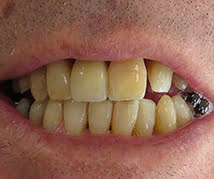

Modern all-ceramic crowns replacing unnatural looking old fashioned crowns with dark metal margins visible.

Before

After